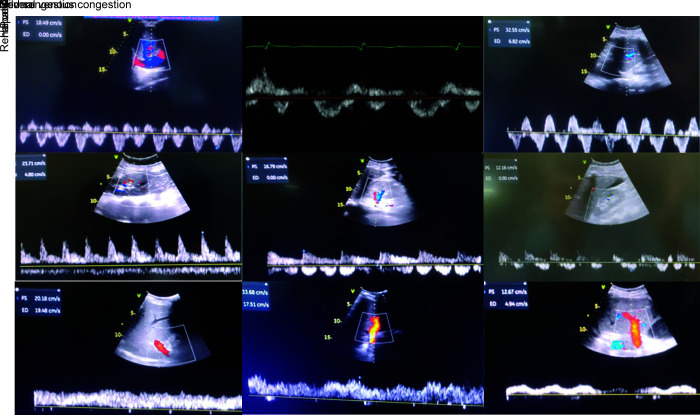

Background: Numerous signs of venous congestion exist, but each has limitations. Previous studies have shown the utility of venous excess ultrasound (VExUS) scoring in predicting acute kidney injury (AKI) in patients postcardiac surgery. This study aimed to evaluate whether serial VExUS scoring could predict AKI in intensive care unit (ICU) patients without cardiac conditions.

Materials and methods: This single-center observational study was conducted in the main ICU of PGIMER, Chandigarh, India. Thirty patients with an inferior vena cava (IVC) diameter of ≥2 cm and a normal biventricular function were included. Serial VExUS scoring was performed on admission and daily for up to six days or until AKI developed, whichever occurred first.